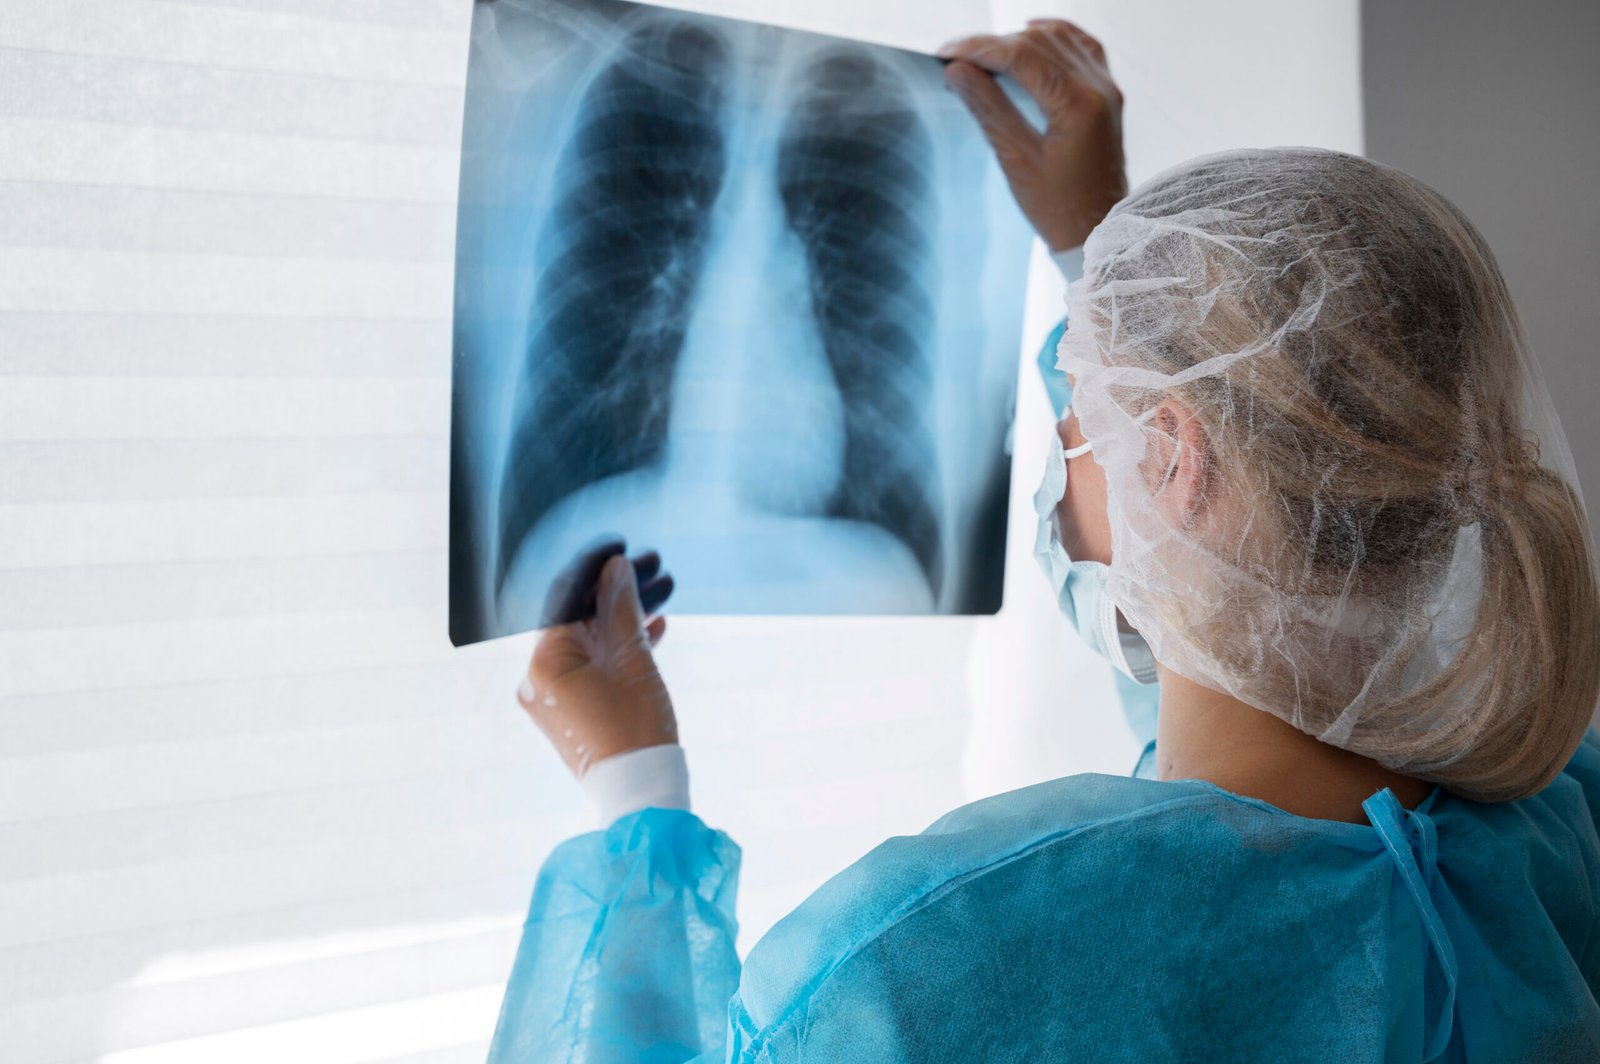

Diagnóstico avanzado y tratamiento personalizado

Cuidando tu salud respiratoria.